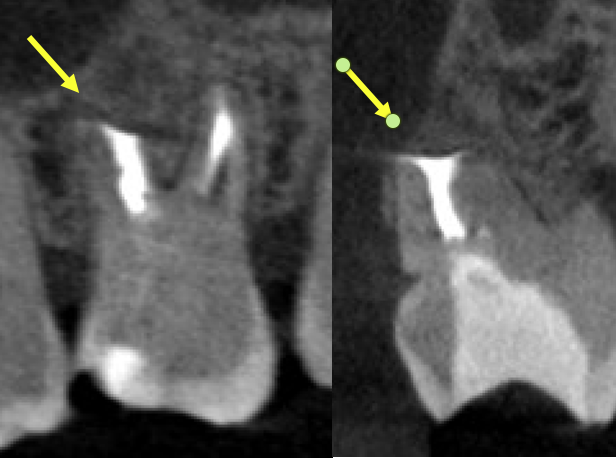

今回のケースは再治療となると3回目となること、過去2回の治療で拡大できていない極度の石灰化根管で難症例であること、被せて3年しか経っていないクラウンを壊したくないこと、確実に治したいけど抜歯はまだしたくない、とのことで歯根端切除術のみで対応したケースです。

過去に根管治療を行った奥歯の歯茎がまた腫れてきた

こちらの患者さんは右上の第一大臼歯を過去に2回根管治療しています。2回目は3年前でラバーダムを使用した自費の精密根管治療だったとのことです。術後経過はよく、自費のセラミッククラウンも装着しましたが3年経過でまた腫れが再発し、歯内療法専門医である当院を受診されました。

• 術前のCBCT画像、右上6の近心頬側根に大きな透過像(炎症の黒い影、赤矢印)があり、腫れの原因となっていることがわかる。未処置の根管、MB2(黄色矢印)は極度に石灰化していて根管のアウトラインも見られない。過去のラバーダム使用の自費の治療でもこういった部分が殺菌できないと病気を治すことは難しい。当院の再治療で石灰化根管の処置が可能かどうかは行ってみないとわからない、また上のケースのように殺菌ができても治らない場合もありえるため、より確実な方法として歯根端切除術を行うこととなりました。

• 治療時画像、黄色矢印はMB1の根管、緑矢印部がMB2があるであろう場所ですが、根管らしきものは石灰化のため見えません。

• もう少し歯根を切断すると、イスムス(黄色矢印)が出てきました。感染源です。

• MB1ごとイスムスを超音波の器具で取り除いているところ。

• 未処置の感染部分の除去後、お薬(バイオセラミックパテ)を充填したところ。

• 術後1年の経過観察時のCBCT画像。治療前の炎症増は無くなり骨の再生が見られ経過良好です。石灰化MB2の部分に充填がなされていることがわかります(黄色矢印)。このように、感染除去を行って、しっかり封鎖をすることで根管治療を繰り返しても治らない難症例も治癒に導くことが可能です。